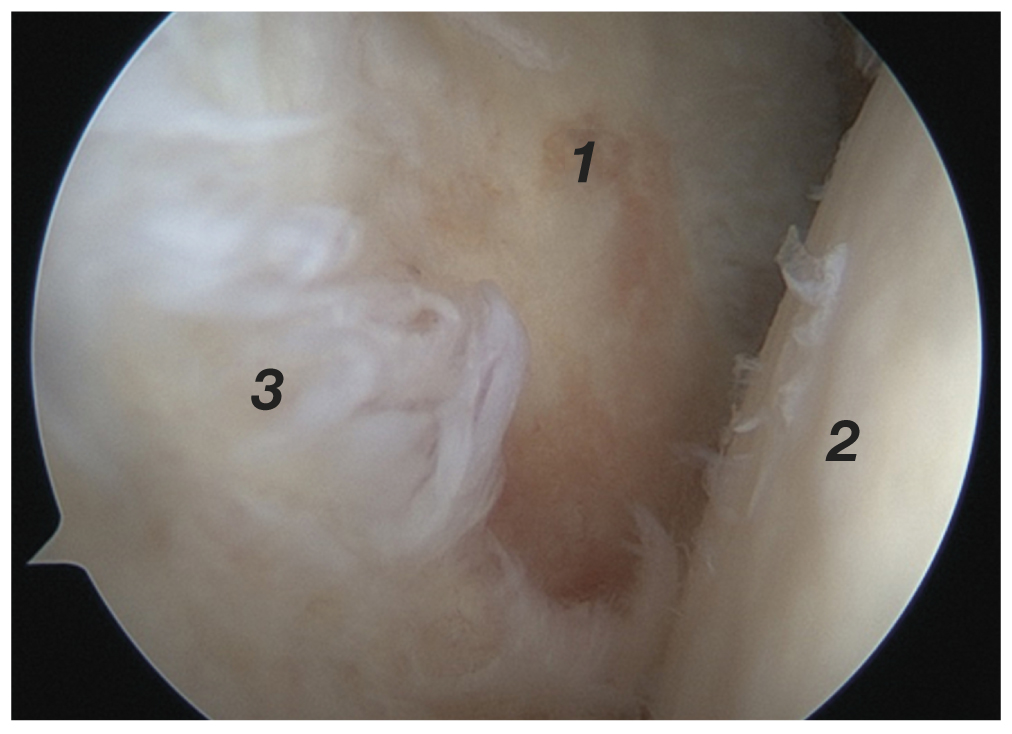

Техника комбинированного эндоскопического вмешательства подразумевает одномоментный ортопедический (артроскопия плечевого сустава) и нейрохирургический (эндоскопический невролиз) компонент. Операцию выполняли в положении пациента «пляжное кресло» под общей анестезией (эндотрахеальный наркоз). Использовали стандартную 30° оптику и стандартное оборудование для артроскопии крупных суставов. Доступ в полость сустава начинали с установки стандартного заднего порта в области «мягкой точки» [13]. Производили диагностическую артроскопию плечевого сустава с оценкой внутрисуставных структур (рис. 1).

Рис. 1. Эндоскопическая картина плечевого сустава: 1 — суставной отросток лопатки; 2 — головка плечевой кости; 3 — дегенеративно-измененная задняя фиброзно-хрящевая губа. / Fig. 1. Endoscopic view of the shoulder joint: 1 — glenoid; 2 — humeral head; 3 — degenerated posterior labrum.